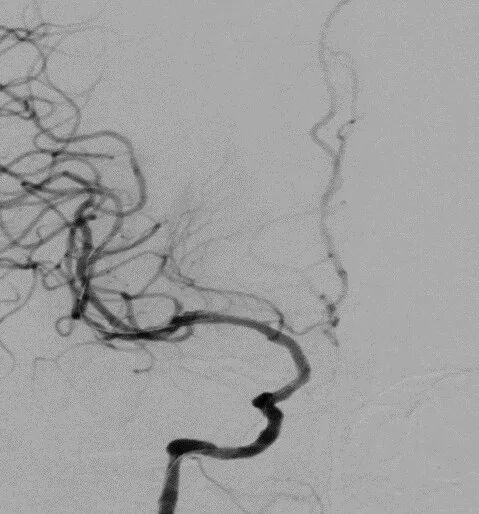

2021-12-3 DSA

重要影像结论:2021-6-25右侧基底节区新发脑梗死,2021-12-3提示右侧颈内动脉海绵窦段重度狭窄。